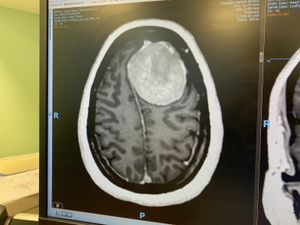

The MRI scan showed a 6cm tumour growing on the left temporal lobe of her brain.

The fact that Helen was walking and talking as she was, left doctors baffled due to the size and placement of the tumour.

Helen added: “The scan showed three shadows within its circular shape which I nicknamed ducky egg and the triplets, I needed to make light of what I had just been told to help me stay positive.”